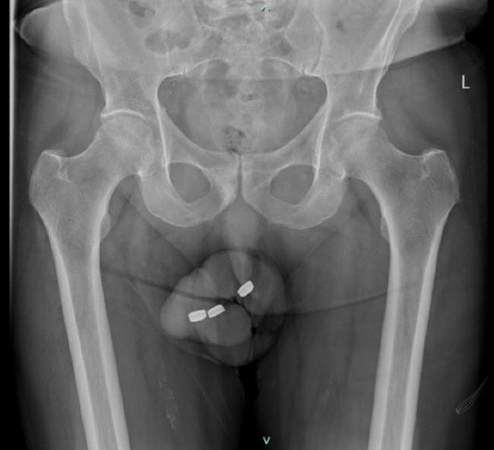

Ο 73χρονος δεν ήταν η πρώτη φορά που χρησιμοποίησε μπαταρίες αλλά αυτή τη φορά έβαλε τρείς… οι οποίες κόλλησαν και δεν έβγαιναν… με αποτέλεσμα να νεκρωθεί η ουρήθρα του. Μετά από ένα 24ωρο ζήτησε βοήθεια και οι γιατροί προχώρησαν σε επέμβαση άμεσα καθώς έπρεπε να αφαιρεθούν οι μπαταρίες γρήγορα γιατί εάν διαβρώνονταν θα προκαλούσαν νέκρωση στους ιστούς μέσα σε μόλις δύο ώρες ενώ παραμόνευε και ο κίνδυνος της γάγγραινας.

Ο άνδρας αφού αφαιρέθηκαν οι μπαταρίες επέστρεψε στο σπίτι όμως έπειτα από δέκα ημέρες πήγε ξανά στο νοσοκομείο με πρήξιμο και πόνους. Οι γιατροί τον ξαναέβαλαν στο χειρουργείο και αναγκάστηκαν να αφαιρέσουν μέρος της ουρήθρας.